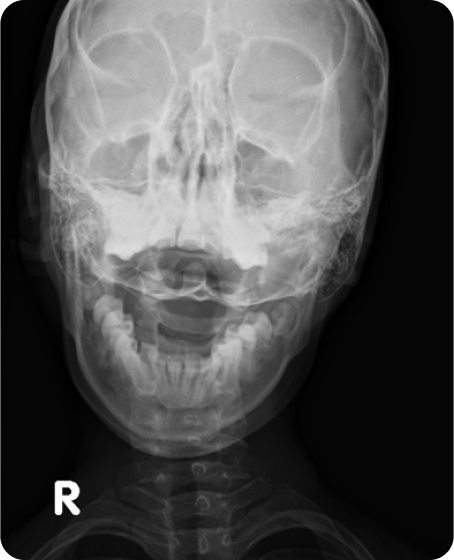

▲ 치료 전 (2016년 1월 21일)